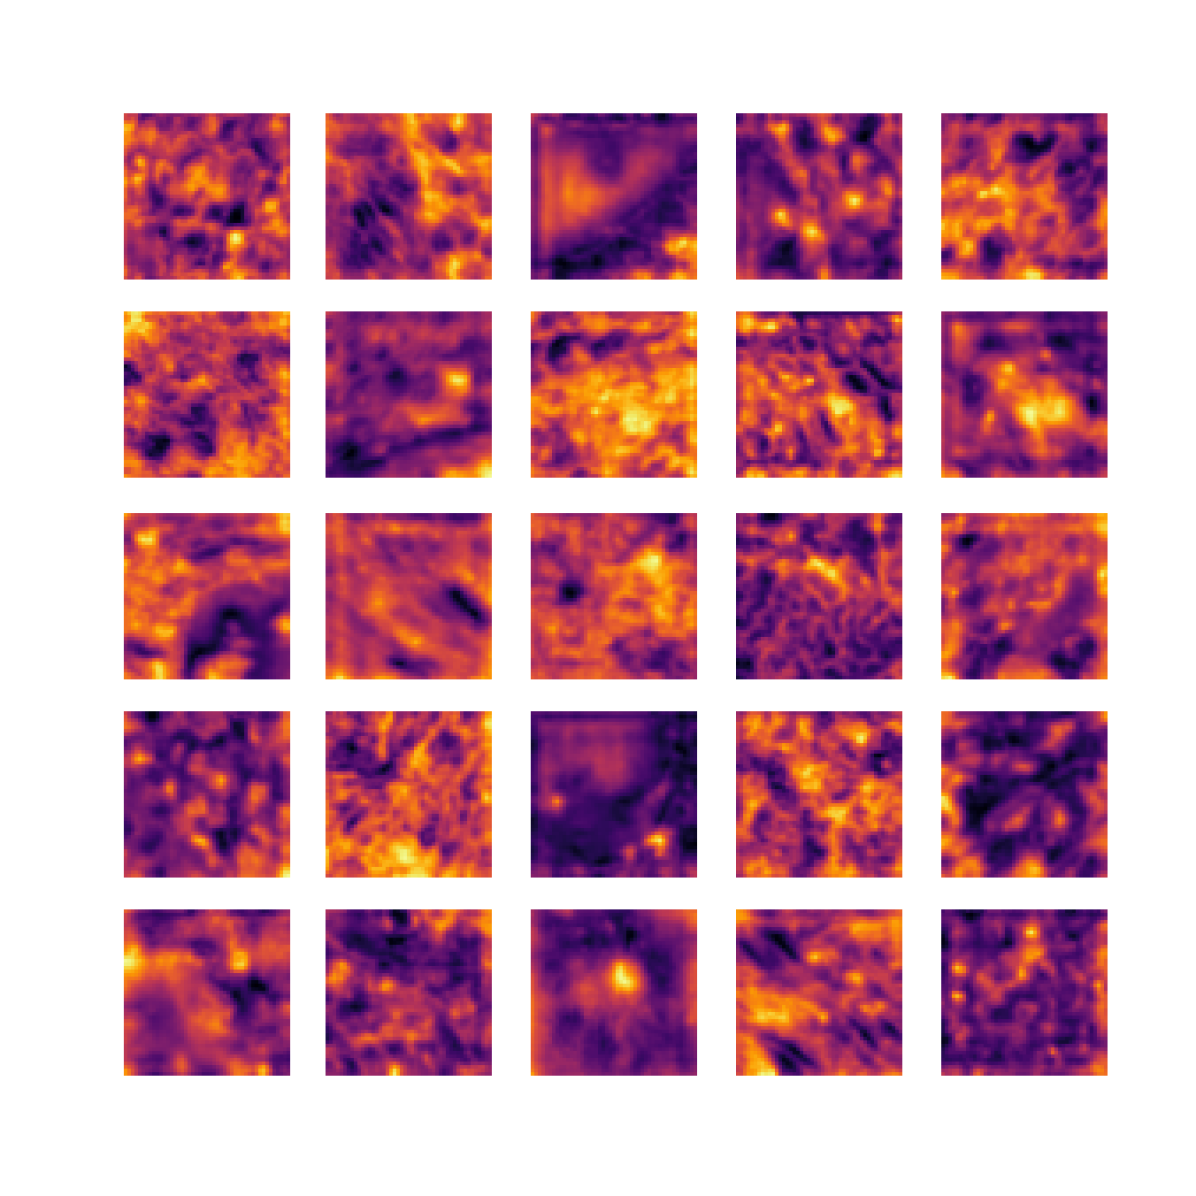

We also analyse the activation maps for each model using GradCAM as described in section S3. This offers more insight into the areas of the image which are contributing most heavily to the models’ representations. In Figure 4(b) we present some representative examples, however, a larger selection which was chosen at random is presented in Figures S10 to S25. The larger selection makes it easier to see the emergent patterns, including that privileged Siamese models tend to mainly identify features which are strongly present in both inputs, while unprivileged Siamese models tend to learn more diffuse features that are not specific to one cell phenotype or image region. TriDeNT ♆ incorporates both sets of features, learning both features specific to the privileged data and more the general features associated with unprivileged Siamese networks.

We can see in Figure 4(b) panel A that for ERG, the privileged Siamese model focuses almost exclusively on any nuclei which could be endothelial cells. As there are very few endothelial cells in the dataset, it could be an effective strategy to identify anything that could potentially be an endothelial cell to minimise the difference between the representations of the H&E model and the IF mask model. In the corresponding unprivileged Siamese image, we see that the model identifies some of these nuclei, albeit less strongly, but also focuses heavily on the other tissue and even the background, while strongly fixating on two spots of debris in the center of the image. This model has less ‘incentive’ to learn the weak features related to endothelial cells as these occur rarely and are not easy to detect, while more generic strong features such as the presence of connective tissue and the prevalence of background are more common and predictable from augmented images. We see that TriDeNT ♆ combines these two feature sets, strongly identifying nuclei while also identifying the connective tissue.

In panel C we see a similar pattern, with the privileged Siamese model fixating solely on the nuclei, while the TriDeNT ♆ model takes a more balanced approach. The unprivileged Siamese model appears to focus on a single cluster of nuclei while neglecting others, and similarly identifies an area of fibroblasts with its distinctive pattern but does not others.

In contrast to panels A and C which represent models with poor privileged Siamese results, panels B and D represent models whose privileged Siamese results were comparable to both TriDeNT ♆ and even the supervised baseline. It is therefore interesting to note that there are far more similarities between the privileged Siamese and TriDeNT ♆ models in both cases. Particularly in panel B, TriDeNT ♆ and the privileged Siamese model return virtually identical heatmaps, with both strongly identifying epithelial nuclei and neglecting the same areas of connective tissue. The unprivileged model in this case appears to focus solely on the centre of the image, giving a significantly different heatmap to the other panels.

Panel D again shows the previous pattern, with the privileged Siamese model identifying the features strongly present in the privileged data – fibroblasts – while neglecting the nuclei present. TriDeNT ♆ also strongly identifies the connective tissue, but, unlike the privileged Siamese model, does not completely neglect the nuclei. The unprivileged Siamese model primarily identifies background, and does not appear to identify the nuclei in this example.